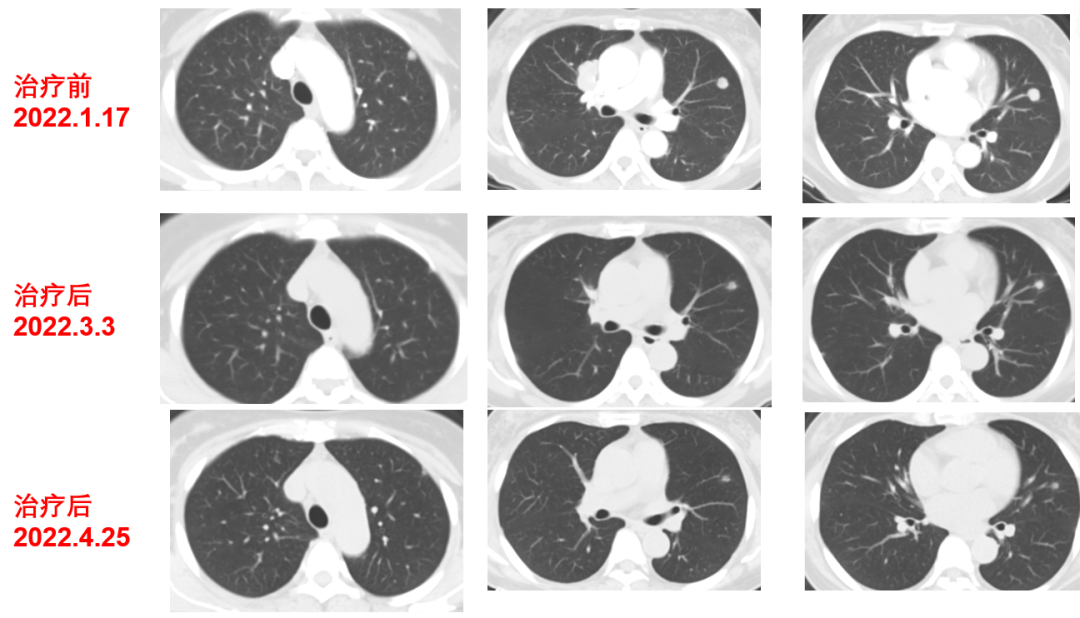

于2021-12-03、2021-12-27给予伊尼妥单抗+吡咯替尼方案治疗2周期。2022.1.19始给予患者伊尼妥单抗+吡咯替尼+替雷利珠单抗治疗,两周期,四周期时的疗效评估可以看到,肺上病灶明显缩小,甚至有的病灶消失,肿瘤标志物也在持续下降。